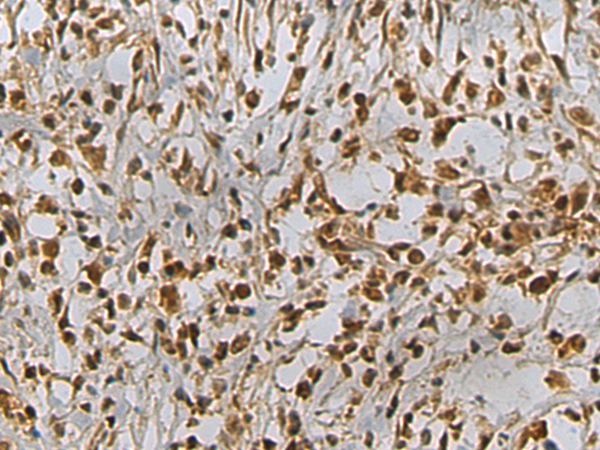

分类: 科研抗体货号: P10061别名: Ntra; KILON; IGLON4; DMML2433应用: WB,IHC反应种属: Human, Mouse, Rat